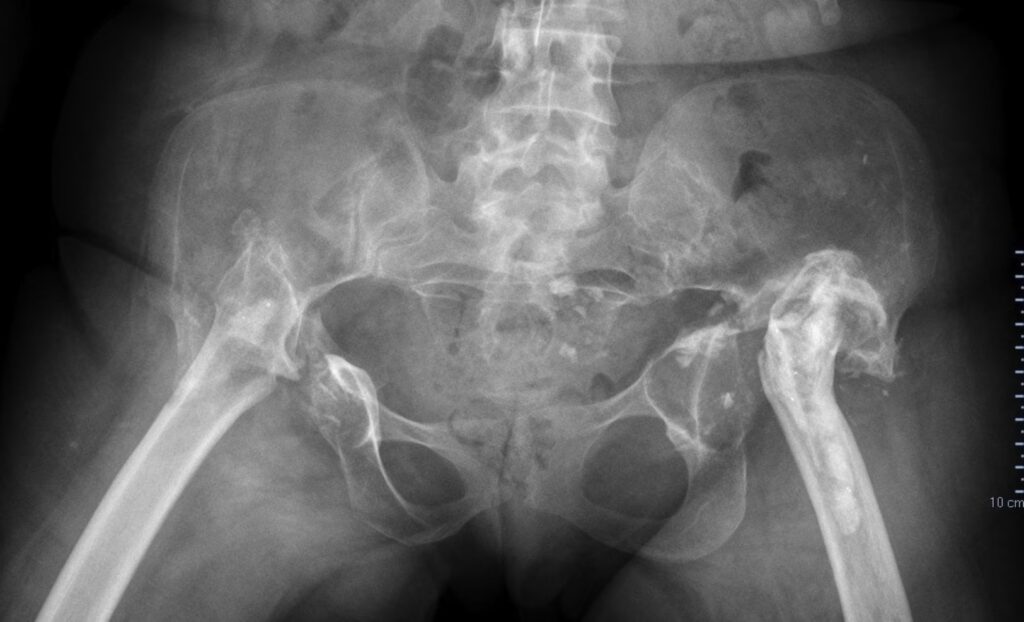

La operación de Girdlestone es una artroplastia por escisión de la cabeza femoral. En términos sencillos, consiste en la extirpación quirúrgica de la cabeza y una porción del cuello del fémur, sin reemplazar estas estructuras con un implante. El objetivo principal de este procedimiento no es recrear una articulación móvil y funcional como en una prótesis de cadera, sino eliminar el foco de la enfermedad (especialmente la infección) y permitir que el espacio entre el fémur y la pelvis se llene de tejido fibroso, creando una especie de nueva “articulación” o, más precisamente, una pseudoartrosis. Esta pseudoartrosis fibrosa, aunque no es una articulación verdadera, permite cierto grado de movimiento y, lo más importante, ayuda a aliviar el dolor.

Históricamente, Girdlestone desarrolló esta técnica a principios del siglo XX como un tratamiento para la tuberculosis de cadera, una enfermedad devastadora en esa época que causaba destrucción articular y abscesos. Su enfoque permitía eliminar el hueso infectado, drenar las colecciones purulentas y crear un ambiente más favorable para la curación. Con el avance de la medicina y la aparición de los antibióticos, la tuberculosis de cadera disminuyó, pero el principio de la artroplastia por escisión encontró nuevas aplicaciones en la era moderna de la ortopedia, particularmente en el manejo de las infecciones protésicas de cadera y otras condiciones complejas.

Hoy en día, la Girdlestone es considerada un procedimiento de “rescate” o “salvamento”. No es la primera opción para la artrosis de cadera estándar, que se trata con artroplastias totales de cadera, sino una solución para situaciones extremas donde la preservación o reconstrucción articular no es posible o segura.